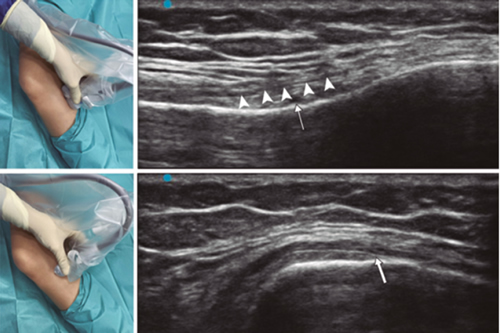

Figure 1

Figure 2

Figure 3

Figure 4

Figure 5